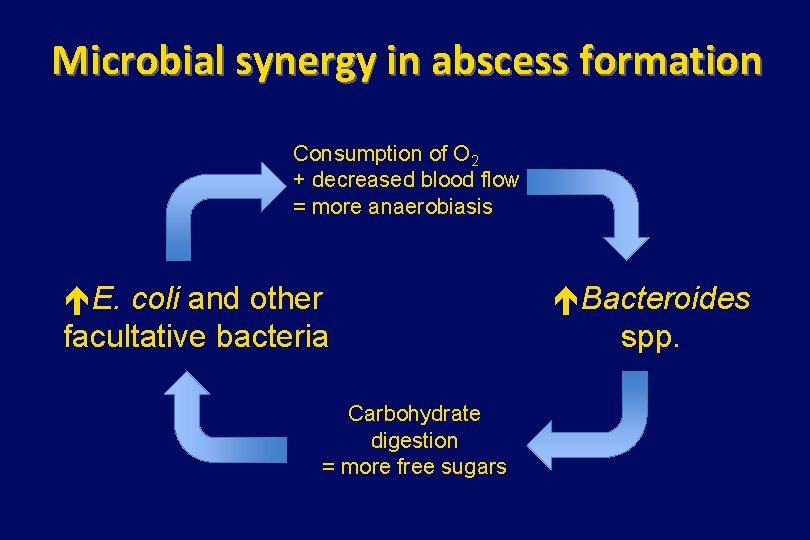

Microbial synergy in abscess formation Consumption of O 2 + decreased blood flow = more anaerobiasis E. coli and other facultative bacteria Carbohydrate digestion = more free sugars Bacteroides spp.